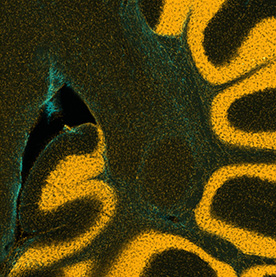

Many processes within the body are changed by the presence of cancer. These images show the response of microglia, immune defense cells in the brain, to cancer cells. When microglia encounter glioblastoma multiforme, one of the most aggressive brain cancers, they shift from a relaxed, elongated shape to a rounded, ready-for-combat conformation.

These images echo the work of Anna Atkins, a British botanist and photographer who used a contact printing technique called cyanotyping to capture the form of plants and algae. Emily Chen’s work similarly seeks to explore biological function, in this case the immune response to brain cancer, by capturing and comparing biological forms.

This triptych shows three views of the folds of a mouse cerebellum, a part of the brain that helps control fine motion. In this form of artwork, the three panels create a story by highlighting a central figure with supporting imagery to either side. This triptych highlights the use of different stains for different features: yellow for the DNA inside brain cells, blue for support cells surrounding neurons. By layering multiple stains, researchers can understand how those elements interact in living tissues.